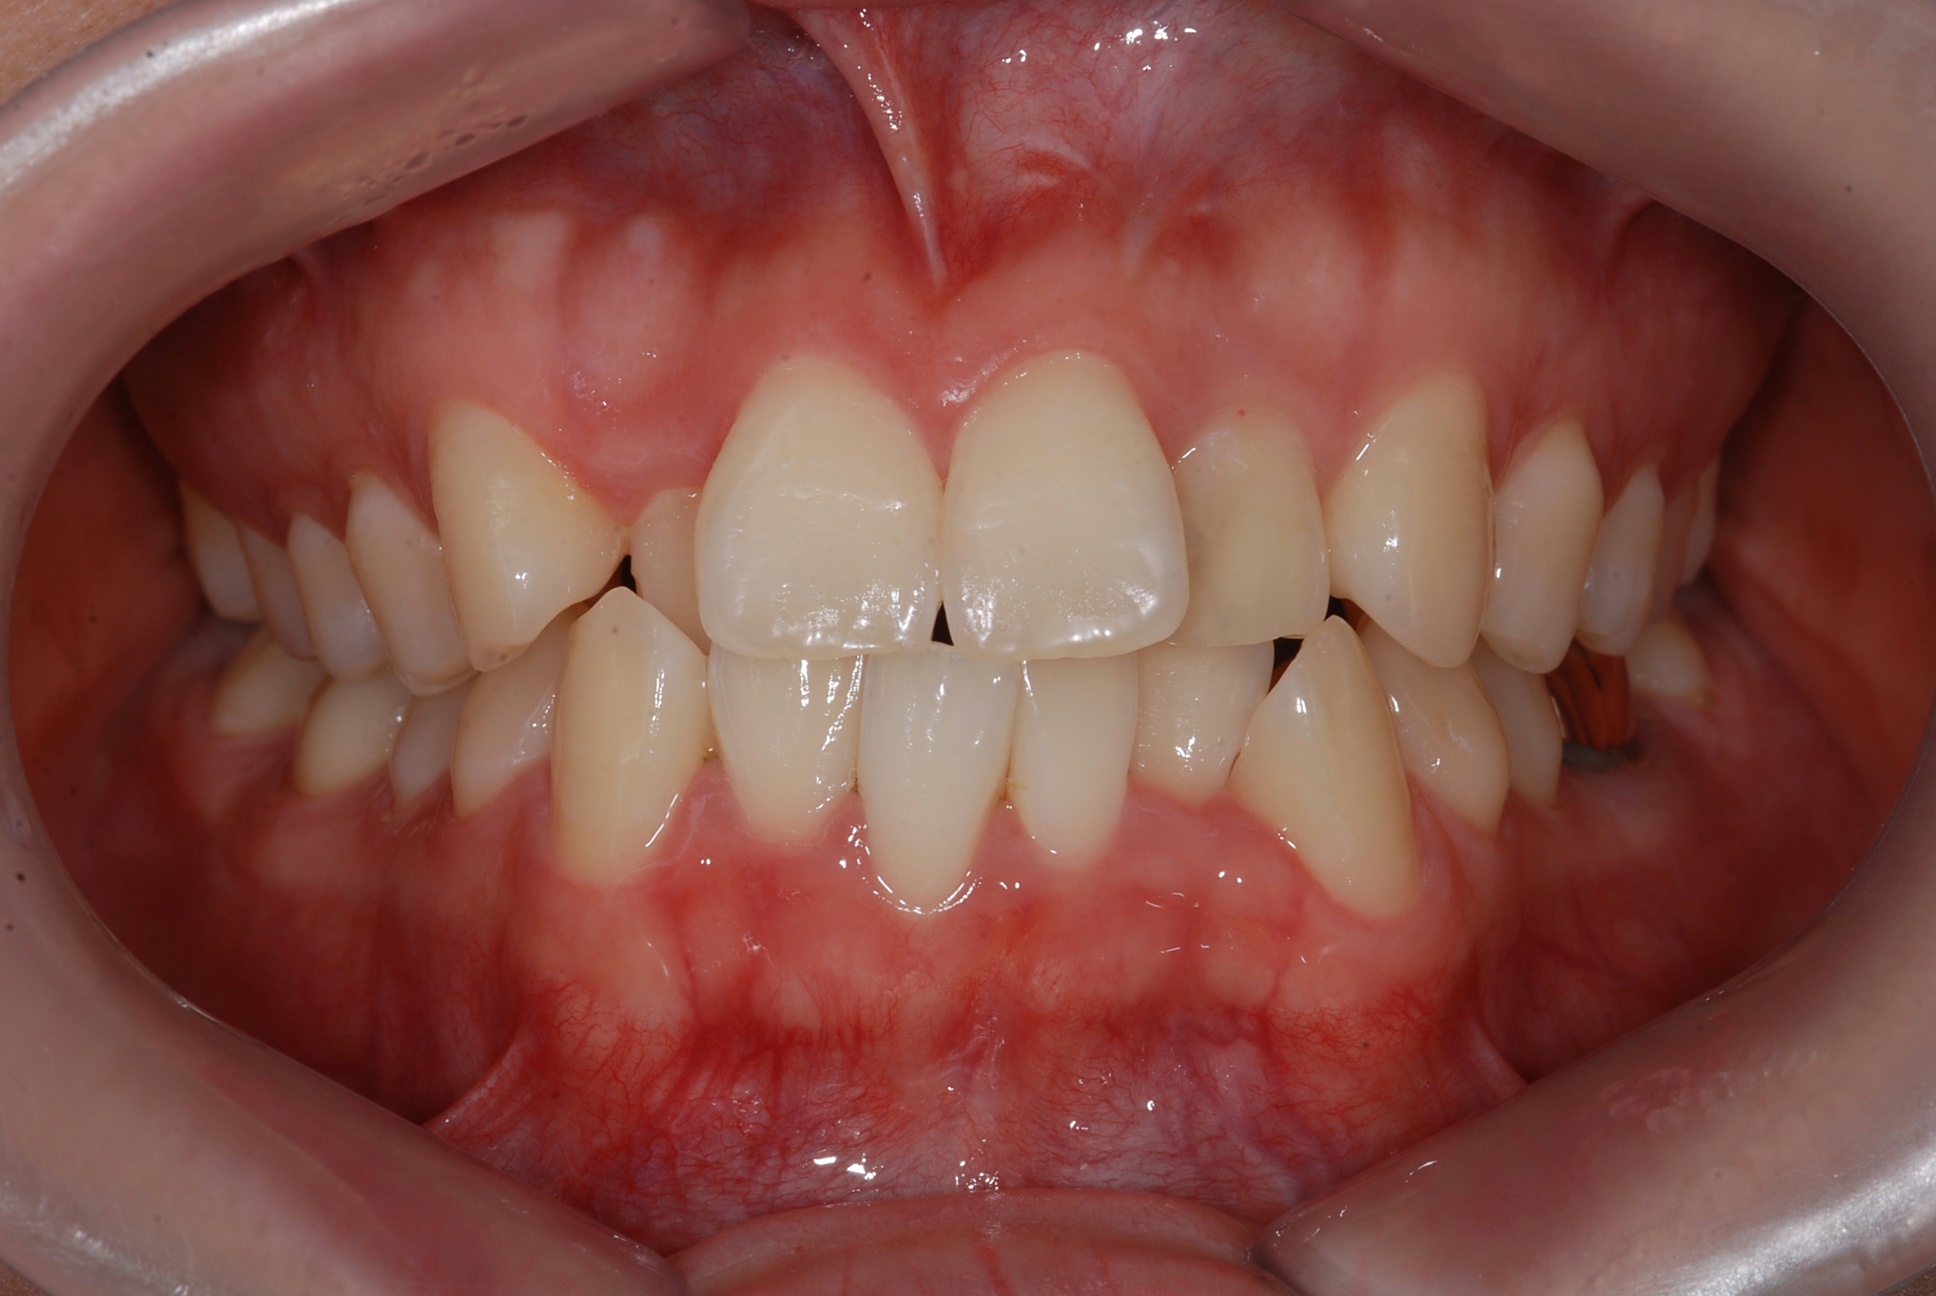

치료 후 사진입니다.